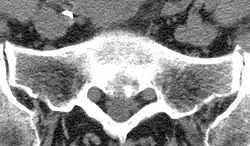

Als Duralsack oder Durasack wird im klinischen Sprachgebrauch der Schlauch aus harter Hirnhaut (Dura mater) bezeichnet, der das Rückenmark und die abgehenden Nervenwurzeln umgibt. Anatomisch ist diese Bezeichnung nicht völlig korrekt, da nicht berücksichtigt wird, dass auch die sogenannte Spinngewebshaut (Arachnoidea) an der Bildung dieser Umkleidung beteiligt ist. Der Duralsack endet auf Höhe des zweiten Sakralwirbels im Filum terminale.

Die Dura mater ist eine solide Hülle, die das hochempfindliche Nervengewebe des Rückenmarkes gegen mechanische Schäden schützen soll. Am Abgang der Nervenwurzeln bildet die Dura jeweils eine Ausstülpung, Wurzeltasche genannt, die die Nervenwurzel begleitet und erst dann in die bindegewebige Hülle des Nervs, das Epineurium, übergeht. Zudem ist der Duralsack mit Rückenmarksflüssigkeit (Liquor cerebrospinalis) gefüllt, auch hier wird eine Schutzfunktion, diesmal im Sinne eines Wasserkissens, angenommen.

Der Duralsack bietet eine recht einfache Möglichkeit, durch Punktion den Liquorraum zu erreichen. Die labortechnische Analyse der Rückenmarksflüssigkeit kann Aufschluss in Bezug auf die Diagnostik einer Reihe von Erkrankungen liefern. Genauso gut ist es aber auch möglich, ein Röntgenkontrastmittel in den Duralsack zu spritzen und damit Raumforderungen innerhalb des Spinalkanals, aber auch krankhafte Veränderungen an den Nervenwurzeln oder am Rückenmark selber festzustellen. Mit dem inzwischen erreichten hohen technischen Entwicklungsstand der Computertomografie und Kernspinresonanz-Diagnostik wird diese Röntgenkontrastdarstellung oder Myelografie immer seltener notwendig. Es ist auch gebräuchlich, Medikamente direkt in den Duralsack zu injizieren, als Möglichkeit, eine völlige Betäubung der unteren Körperhälfte zu erreichen (Spinalanästhesie), um hier Operationen durchführen zu können. In der Geburtshilfe wird meistens ein Betäubungsmittel nur in den Raum zwischen Dura und Wirbelkanal eingebracht (Periduralanästhesie).